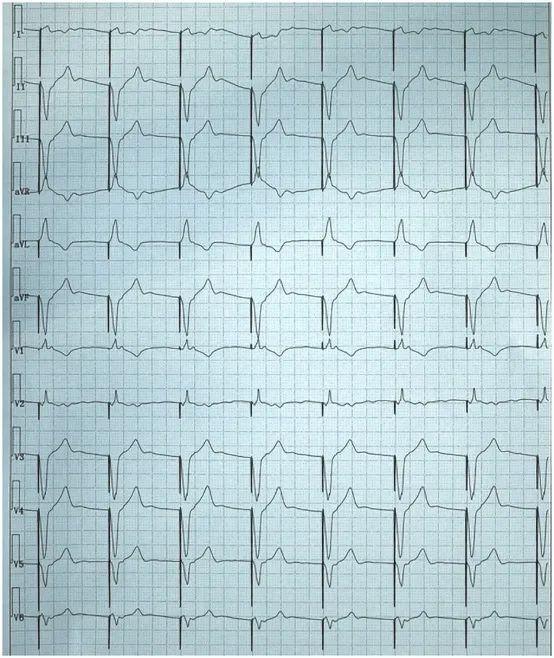

患者,女性,73岁,既往因病态窦房结综合征而植入右室单腔起搏器,此次门诊复诊行心电图检查如下。

图1. 患者门诊心电图呈VVI起搏(心率60次/分)。

大家可能关注到,患者此次复诊的心电图V1导联的QRS波向上,呈类“RBBB”样图形,和平常我们认为右室起搏时心电图呈类“左束支传导阻滞(LBBB)”的图形相反,难道是电极穿孔了?我们的“福尔摩斯医生”看到这份心电图,肯定地说没有穿孔,电极是在右室,而随后患者的胸片和胸部CT检查也证实了电极确实是在右室。

学习到这里,回到最开始的病例,该患者心电图的额面电轴位于左上象限,胸前移行导联≤V3。相信凭借大家的“火眼金睛”,此时也能一眼看出电极的位置是位于右室。这项技能你get了吗?